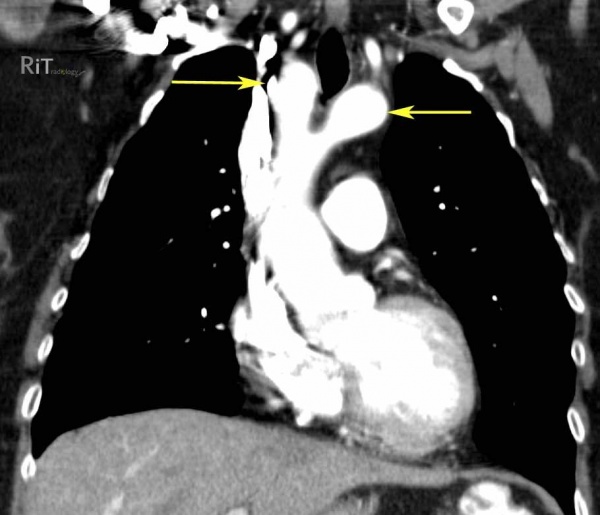

Мультиспиральная компьютерная ангиография аорты и магистральных сосудов рекомендуется для получения трехмерного изображения, на котором отчетливо видна двойная сосудистая дуга. Используя МСКТ, диаметр аорты измеряется на разных уровнях, и определяются области атрезии.

КТ сердца. Двойная дуга аорты. Стрелки указывают на правую и левую дуги аорты примерно одинакового размера.